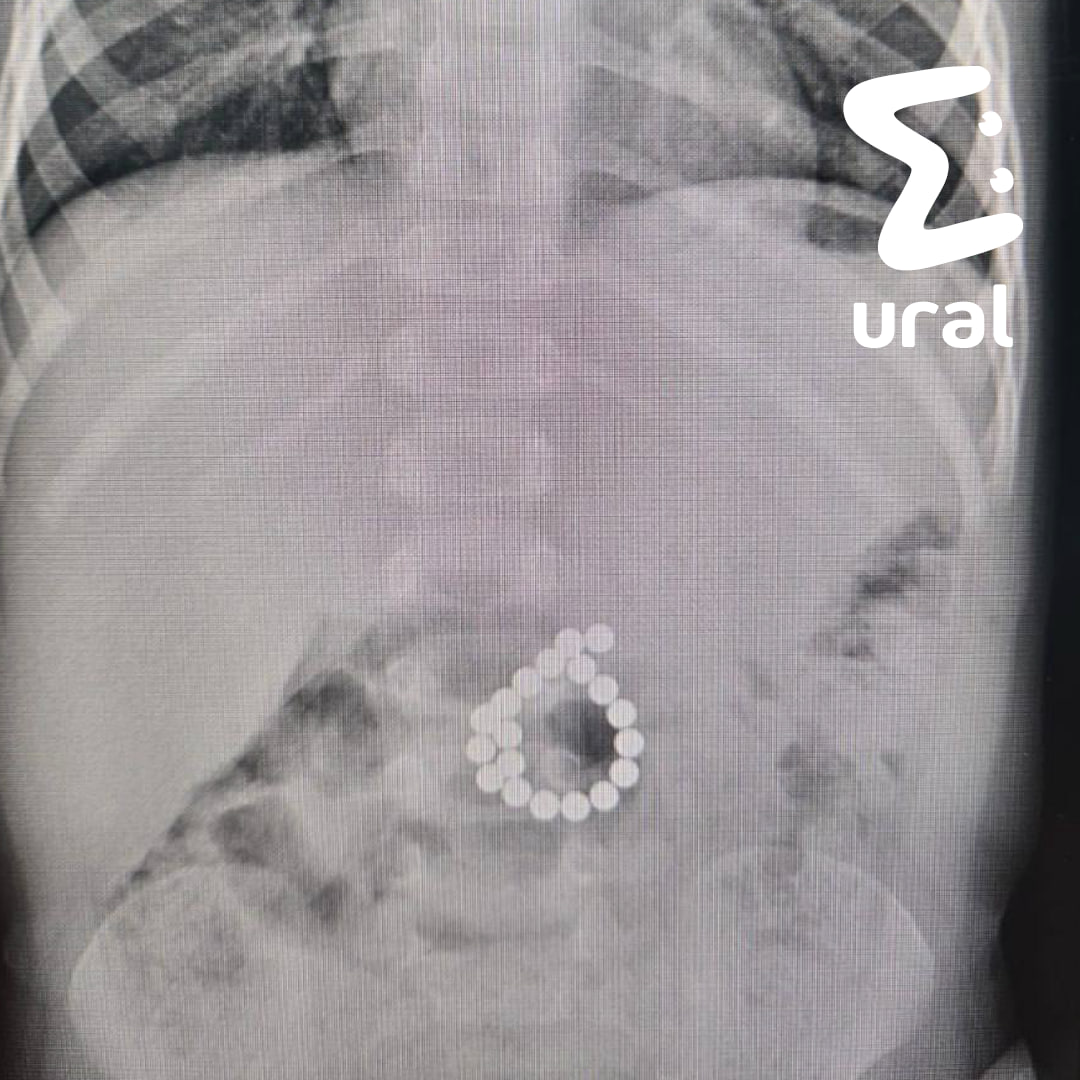

В ХМАО двухлетний мальчик проглотил магнитный конструктор и чуть не погиб.

Ребёнка привезли к врачам с высокой температурой и резкими болями в животе. Оказалось, несколько дней назад малыш играл с игрушкой и проглотил не одну-две детали, а сразу 19 (!). Хирурги быстро удалили магниты, повреждения ушили.